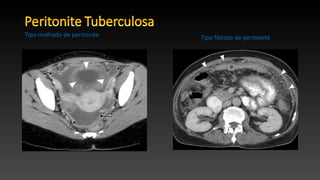

• Manifestação clínica mais comum da tuberculose abdominal, que

afeta um terço de todos os pacientes.

• Originado principalmente da disseminação hematogênica; no

entanto, pode ser secundária a uma rotura de linfonodo, do aparelho

digestivo ou da tuba de Falópio.

• A condição é subdividida em três tipos principais: molhado, fibrose e

seca.

• Tipo mais comum (90% de casos) e dispõe de grandes quantidades de líquido livre ou

septado, ocasionando ascite.

• Na TC, é geralmente ligeiramente hiperatenuante (20-45 HU) em relação à água

devido ao seu alto teor de proteína e células.

• 60% dos casos.

• Na TC, manifesta como massas de baixa atenuação com espessamento do tecido mole

nodular.

• Observada em 10% dos casos, e é caracterizada por espessamento mesentérico,

aderências fibrosas e nódulos caseosos.

• Os achados da TC em peritonite tuberculosa são

inespecíficos.

Tipo molhado de peritonite

Tipo seco de peritonite

Tipo fibroso de peritonite

Tipo molhado de peritonite Tipo fibroso de peritonite

• Manifestação clínicamais comum da tuberculose abdominal, que afeta um terço de todos os pacientes. • Originado principalmente da disseminação hematogênica; no entanto, pode ser secundária a uma rotura de linfonodo, do aparelho digestivo ou da tuba de Falópio. • A condição é subdividida em três tipos principais: molhado, fibrose e seca.

• Tipo maiscomum (90% de casos) e dispõe de grandes quantidades de líquido livre ou septado, ocasionando ascite. • Na TC, é geralmente ligeiramente hiperatenuante (20-45 HU) em relação à água devido ao seu alto teor de proteína e células. • 60% dos casos. • Na TC, manifesta como massas de baixa atenuação com espessamento do tecido mole nodular. • Observada em 10% dos casos, e é caracterizada por espessamento mesentérico, aderências fibrosas e nódulos caseosos. • Os achados da TC em peritonite tuberculosa são inespecíficos. Tipo molhado de peritonite Tipo seco de peritonite Tipo fibroso de peritonite

Tipo molhado deperitonite Tipo fibroso de peritonite